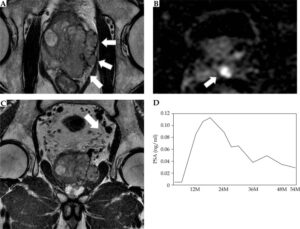

具体的には、本論文が対象とした143例はPSAの平均値が20ng/ml以上でありPSA値が100ng/mlを超える症例も含まれ、ステージでいえばT3a以上 (T3a, T3b, T4) の局所進行前立腺癌症例が63%を占めています。また骨盤内リンパ節転移を伴う症例も5症例含まれています(これらリンパ節転移を有していた5症例はいずれも、後に述べるような全骨盤への外部照射を併用したトリモダリティ治療を行うことにより再発なく経過しています:代表的なリンパ節転移を認める症例として骨盤内を占拠し精嚢浸潤を伴う局所進行前立腺癌T3bN1:治療前PSA=65ng/mlであった症例の完治例が本論文のFigure 2に提示してありますので御覧いただければ幸いです)。

Representative T3bN1 case treated by tri-modality with whole pelvis external beam radiotherapy (EBRT). Case: 68-yearold man with initial prostate-specific antigen (PSA) 65 ng/ml. The needle biopsy Gleason’s score was 4+4. Clinical stage was T3bN1. Magnetic resonance imaging shows (A) a bulky prostate tumor extending over the capsule and compressing the rectal wall (B) with seminal vesicle invasion, and (C) nodal metastasis as indicated by white arrows. The patient was treated by combination therapy with low-dose-rate (LDR) brachytherapy, whole pelvis EBRT, and androgen deprivation therapy (ADT). Upon seeds implantation, they were implanted in seminal vesicle as well as prostate [15]; (D) PSA change after treatment: PSA shows temporal increase after cessation of ADT, but continuous decrease was observed thereafter. Y axis shows the period (months) from completion of the EBRT